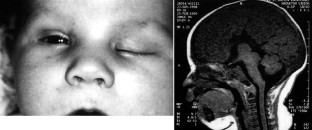

Clinical examination and forced duction testing confirmed that all four patients met criteria for CFEOM; all had congenital restrictive ophthalmoplegia primarily affecting extraocular muscles innervated by the oculomotor nerve. Two brothers had CFEOM and Marcus Gunn jaw winking. In each of the four cases, CFEOM occurred in association with one or several neuroradiological findings, including agenesis of the corpus callosum, colpocephaly, hypoplasia of the cerebellar vermis, expansion of the ventricular system, pachygyria, encephalocele and/or hydrancephaly.

Fig. 1.

Fig. 2.